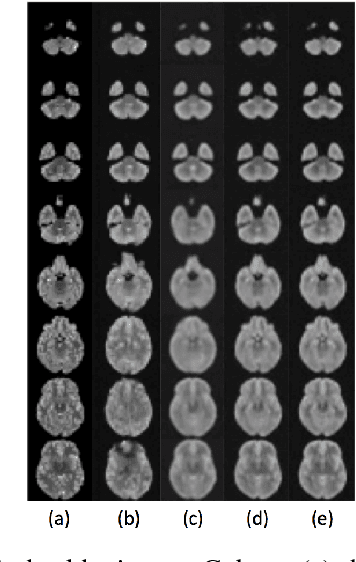

Lesion detection in brain Magnetic Resonance Images (MRI) remains a challenging task. State-of-the-art approaches are mostly based on supervised learning making use of large annotated datasets. Human beings, on the other hand, even non-experts, can detect most abnormal lesions after seeing a handful of healthy brain images. Replicating this capability of using prior information on the appearance of healthy brain structure to detect lesions can help computers achieve human level abnormality detection, specifically reducing the need for numerous labeled examples and bettering generalization of previously unseen lesions. To this end, we study detection of lesion regions in an unsupervised manner by learning data distribution of brain MRI of healthy subjects using auto-encoder based methods. We hypothesize that one of the main limitations of the current models is the lack of consistency in latent representation. We propose a simple yet effective constraint that helps mapping of an image bearing lesion close to its corresponding healthy image in the latent space. We use the Human Connectome Project dataset to learn distribution of healthy-appearing brain MRI and report improved detection, in terms of AUC, of the lesions in the BRATS challenge dataset.